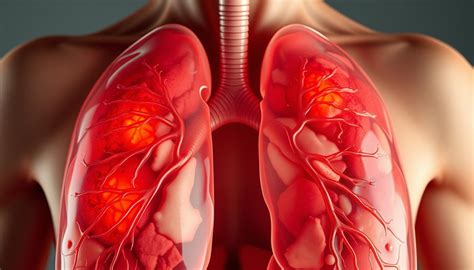

Plaučių uždegimas, dar vadinamas pneumonija, yra infekcinė kvėpavimo takų liga, kuri paveikia plaučių audinį, ypač alveoles. Plaučių uždegimas - tai infekcija, pažeidžianti plaučių audinį ir apsunkinanti kvėpavimą. Esant uždegimui, alveolės užsipildo skysčiais ar pūliais, todėl plaučiai praranda gebėjimą tinkamai atlikti savo pagrindinę funkciją - užtikrinti efektyvų deguonies tiekimą organizmui. Plaučių uždegimu susergama, kai mikrobai patenka į plaučius ir sukelia infekciją. Imuninės sistemos reakcija į infekciją sukelia plaučių oro maišelių (alveolių) uždegimą. Ši liga gali būti sukelta įvairių patogenų: bakterijų, virusų ar net toksinių medžiagų patekimo į plaučius.

Plaučių uždegimas atsiranda dėl įvairių patogenų, kurie įsiskverbia į kvėpavimo sistemą ir sukelia plaučių audinių uždegimą. Dažniausios plaučių uždegimo priežastys yra bakterijos ir virusai, kurie gali būti perduodami tiesioginio kontakto su infekuotu asmeniu, oro lašeliniu būdu arba netiesiogiai - per užterštus paviršius. Taip pat įtakos turi būklės, susijusios su imuniniais mechanizmais, piktybiniais navikais, tokios ligos kaip lėtinė obstrukcinė plaučių liga, bronchinė astma bei cukrinis diabetas.